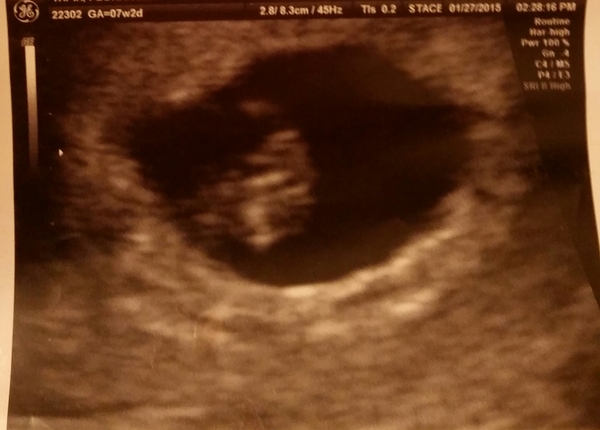

This is my u/s at 7w2d. a regular abdominal u/s.

i was really wondering if anyone could hep me with the Ramzi Theory

and please let me know what you all think! :)

thanks